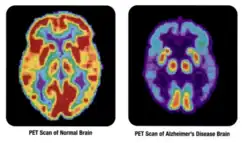

Ядерная медицина применяется в следующих областях (на примере США): кардиология — 46 % от общего числа диагностических исследований, онкология — 34 %, неврология — 10 %[4]. В частности, в онкологии (радиобиология опухолей) ядерная медицина выполняет такие задачи, как выявление опухолей, метастазов и рецидивов, определение степени распространённости опухолевого процесса, дифференциальная диагностика, лечение опухолевых образований и оценка эффективности противоопухолевой терапии[5].

Позитронное излучение фиксируют позитронно-эмиссионные томографы (ПЭТ-сканеры)[16][19].